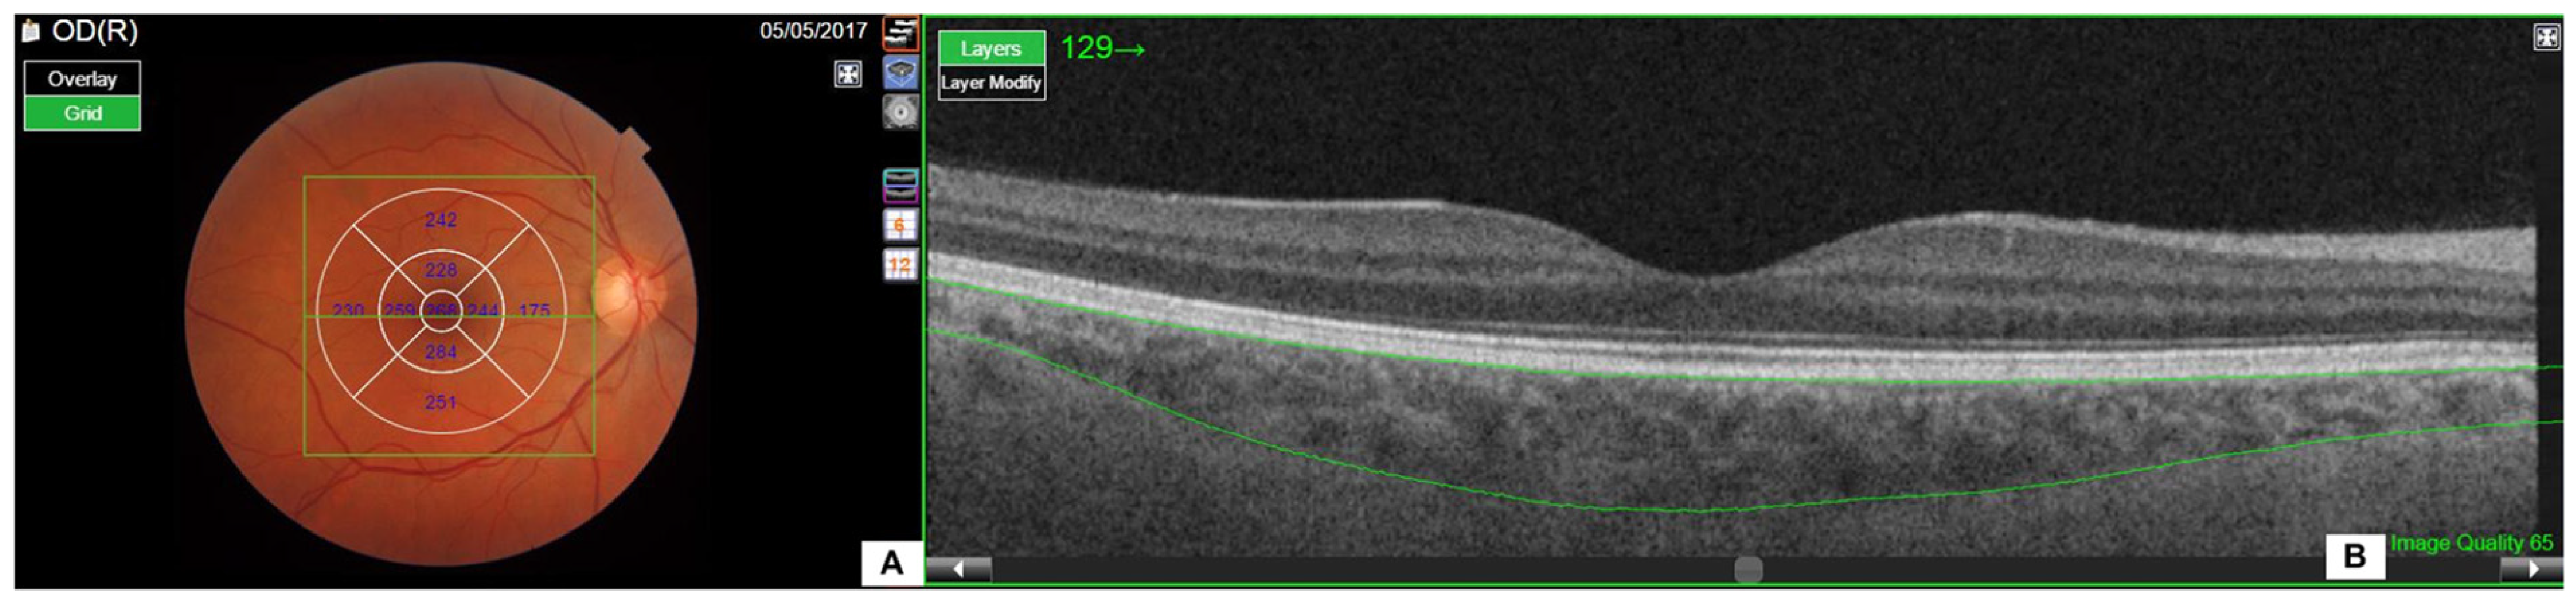

2.1.2. Ophthalmic Examination